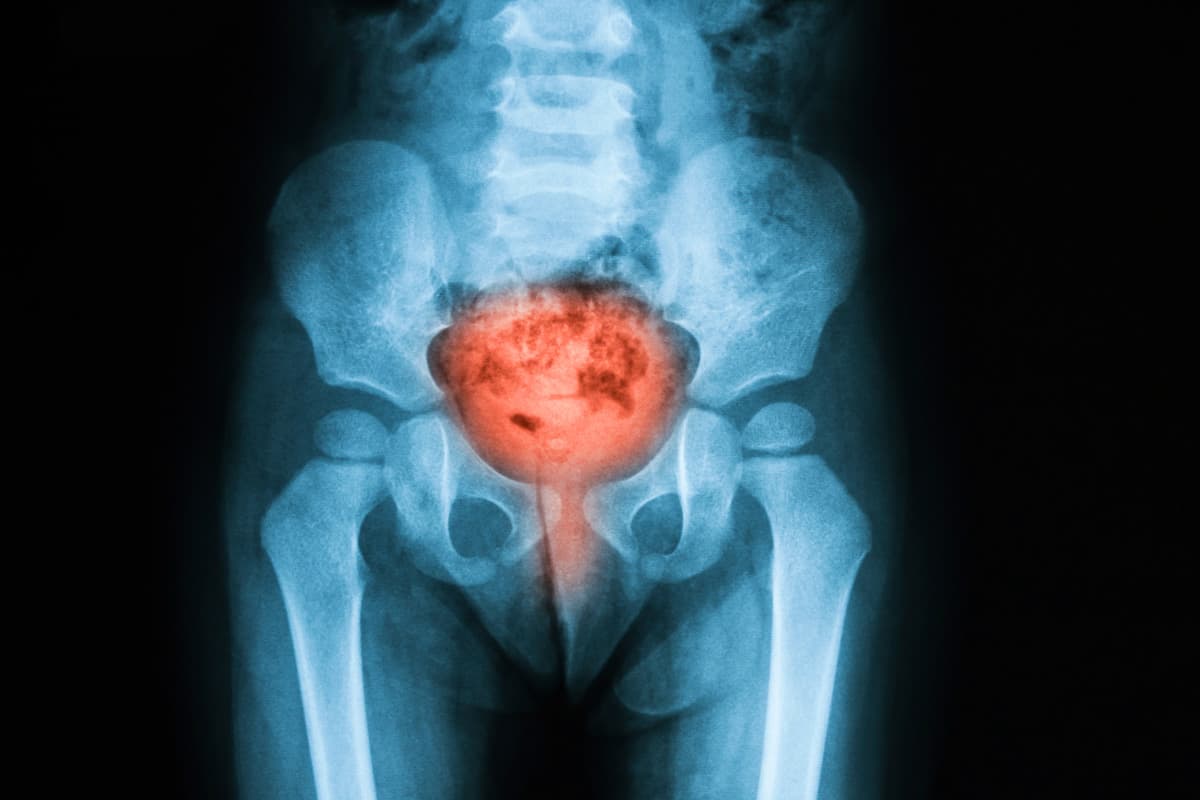

Imaging Studies: In complicated or recurrent UTIs, ultrasound, CT scans, or MRI may assess structural abnormalities or kidney stones.